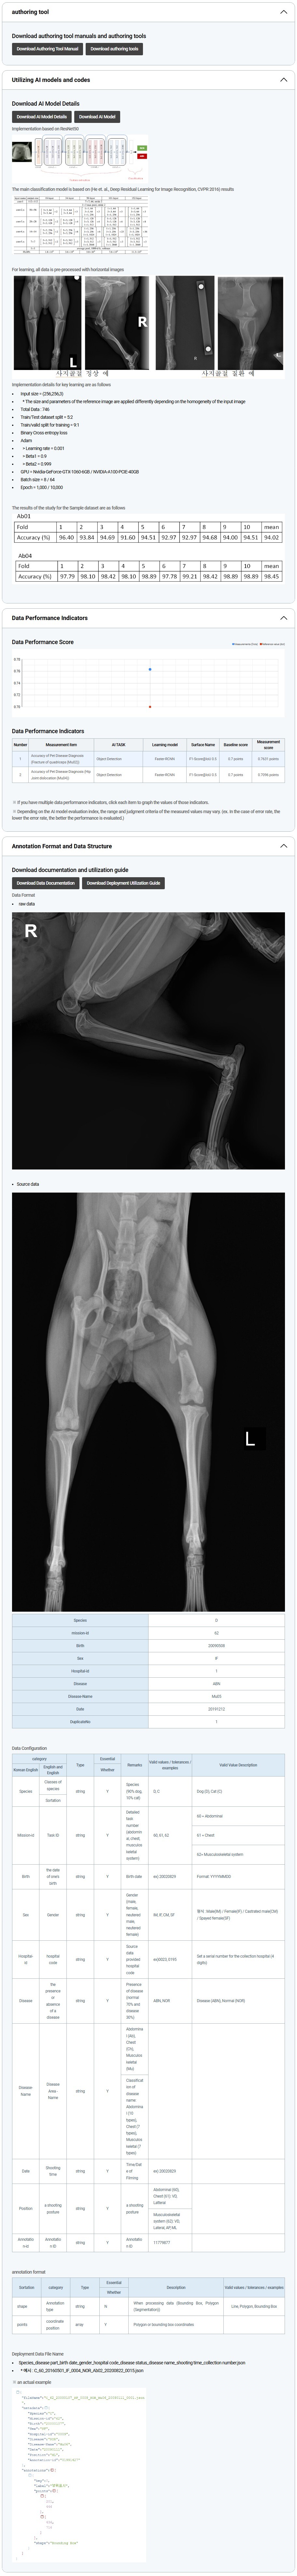

Imaging data for diagnosis of pet diseases (musculoskeletal system)